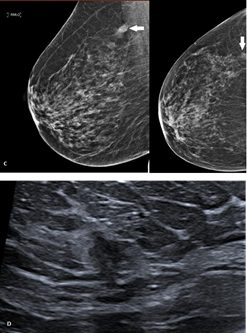

Mammography is the most common imaging modality used to assess breast disease and it is capable of detecting subtle abnormalities such as microcalcifications, architectural distortion and opacities with spiculated margins with a specificity of 55% and sensibility of 70%.9 Recently, computer–aided detection (CAD) has been developed to help radiologists in identifying breast anomalies. It employs a specific computer algorithm capable of individualizing and marking suspicious mammogram findings, assisting the radiologist during the interpretation of the exam.10,11 However, there are some limitations to mammograms, especially breast density that can provoke superimpositions, which are able to hide pathological lesions and avoid detection, even with the use of CAD.4,10 For these reasons, digital breast tomosynthesis has been extensively used in conjunction with mammography. It acquires multiple low dose mammographic projections of the breasts which are organized in stacks of slices after tomographic reconstruction, similar to CT, reducing tissue superimposition and improving detection of masses or architectural distortion (Figure 1).4,12

Figure 1 A. Mammography of the right breast revealed an irregular and spiculated opacity in the outer upper quadrant (white arrow). B. Tomosynthesis performed on the cranio-caudal view (left image) improves characterization of the lesion compared to standard mammography (right image), with better visualization of the spiculated aspect of the lesion.